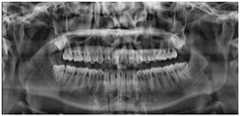

fig. 2 is an overall view of a cheek portion to be weakened according to a specific example of a method for weakening cheek clamp development based on pixel adjustment in the embodiment of the present invention;

Illustratively, the panoramic image to be weakened may be a medical image of multiple modalities acquired by an imaging device such as an electronic computer, magnetic resonance, or the like; in this embodiment, a method for weakening a cheek clamp development based on pixel adjustment described in the present application is described by taking a facial CT image with a cheek clamp development as an example, and fig. 2 is a panoramic view of a portion of a cheek to be weakened, where (1) indicates a left cheek clamp region and (2) indicates a right cheek clamp region.